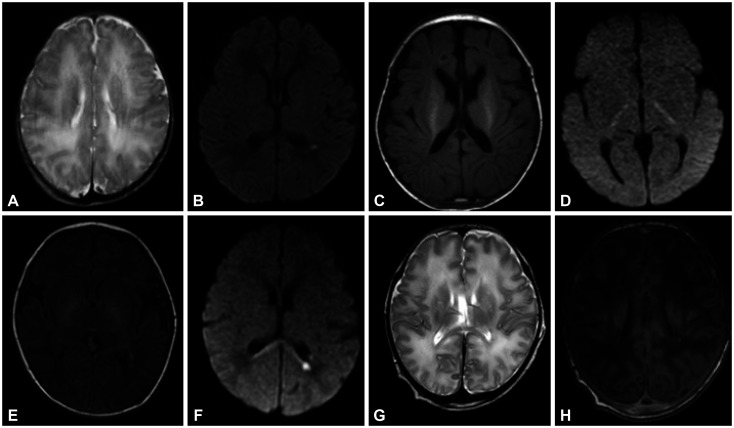

背景和目的:新生儿脑病(NE)是一种神经系统综合征,表现为严重的神经系统损伤和并发症。缺氧缺血性脑病是导致不良预后的主要因素,占新生儿重症监护病房收治病例的 50%-80%。然而,一些伴有缺氧性脑损伤的 NE 病例不能完全归咎于缺氧缺血。我们旨在找出可能与伴有缺氧性脑损伤而非缺氧缺血的 NE 病例相关的各种致病基因变异:我们收集了 34 名被诊断为伴有缺氧性脑损伤的 NE 患者 10 年间的数据。排除了以下特殊情况的患者:1)早产儿(结果:11 例早产儿被确诊为遗传性 NE:11名患者(32.4%)被确诊为遗传病,并在以下9个基因中发现了致病变体:CACNA1A(n=2)、KCNQ2(n=2)、SCN2A(n=1)、SCN8A(n=1)、STXBP1(n=1)、NSD1(n=1)、PURA(n=1)、ZBTB20(n=1)和 ENG(n=1)。除早产外,其他特定治疗结果或临床特征均与基因分析结果无关。根据基因检测结果尝试了个性化治疗,如对KCNQ2或SCN8A变异的患者使用钠通道阻滞剂,对STXBP1或SCN2A变异的患者实施生酮饮食,这在一定程度上对这些患者有效:无论最初的临床特征如何,基因分析都有助于诊断 NE 和并发缺氧性脑损伤的潜在病因。

Results: A genetic diagnosis was made in 11 (32.4%) patients, with pathogenic variants being identified in the following 9 genes: CACNA1A (n=2), KCNQ2 (n=2), SCN2A (n=1), SCN8A (n=1), STXBP1 (n=1), NSD1 (n=1), PURA (n=1), ZBTB20 (n=1), and ENG (n=1). No specific treatment outcomes or clinical features other than preterm birth were associated with the results of the genetic analyses. Personalized treatments based on the results of genetic tests were attempted, such as the administration of sodium-channel blockers in patients with KCNQ2 or SCN8A variants and the implementation of a ketogenic diet in patients with STXBP1 or SCN2A mutations, which demonstrated some degree of effectiveness in these patients.